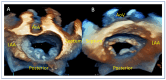

Mitral regurgitation (MR) is a common valvular heart disease associated with significant morbidity and mortality. For patients at high or prohibitive surgical risk, mitral transcatheter edge-to-edge repair (M-TEER) offers a less invasive alternative to surgery. This review outlines key aspects of patient selection and procedural planning for M-TEER, with a focus on clinical and echocardiographic criteria essential for success. Comprehensive imaging-especially 2D and 3D transesophageal echocardiography-is critical to assess leaflet anatomy, coaptation geometry, and mitral valve area. Selection criteria differ between primary and secondary MR and are guided by trials such as COAPT and MITRA-FR. Optimal outcomes rely on careful screening, anatomical suitability, and multidisciplinary evaluation. With growing experience and advancing technology, M-TEER has become a transformative option for treating severe MR in non-surgical candidates.